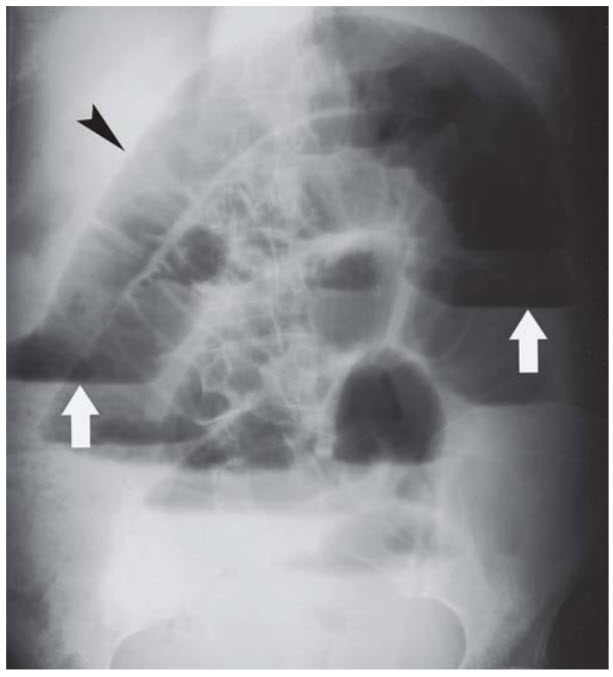

A 66-year-old woman with a history of multiple abdominal surgeries presents with nausea, vomiting, and abdominal pain. Abdominal x-ray is shown in Figure below.

Adhesion formation. This patient is presenting with a small bowel obstruction, which is indicated by the air–fluid levels on x-ray. The most common cause of small bowel obstruction in patients with a history of abdominal surgery is adhesion formation. (A, B, D) These other choices are less common causes of small bowel obstruction.